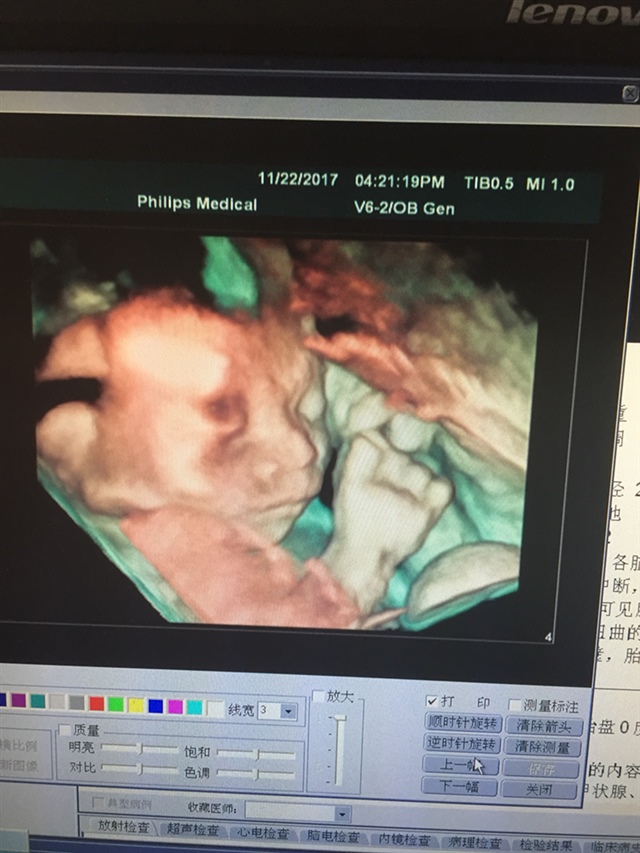

宝宝4个月3天

像你老公多点,在揉眼睛好可爱啊